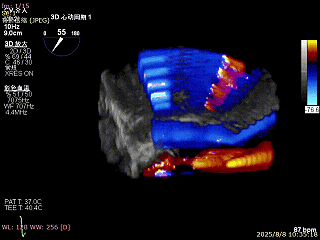

3D enface反流充分降低

术后平均跨瓣压差2mmHg

双孔组织桥稳定